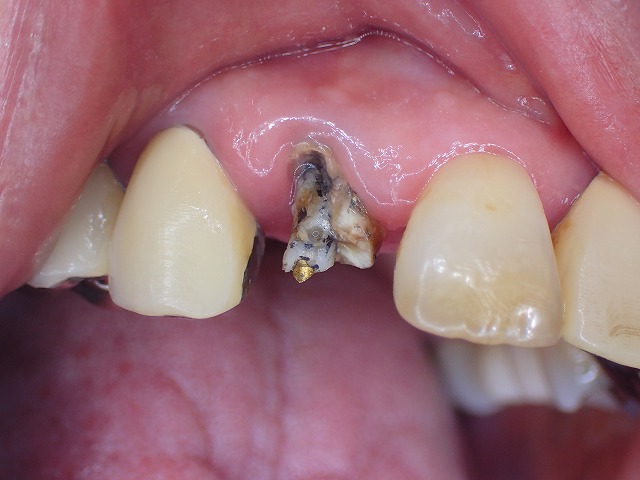

折れた歯の中にはスクリューピン 歯にネジ スクリュ-ピンがらみは状態が悪い

これがあると歯がボロボロのケースが多い

スクリューピンはネジを中心にして、

その周囲をレジンで固めてあります。

しかし、模型を作って制作するわけではないので

歯質とはきちんと適合しないばかりか

周囲のレジンが破損するため

トラブルリスクが高くなります。

装着されていたかぶせ物

中はひどい状態

ネジを除去すするとみての通り壊滅的状態 これが何だかわかりますか?

除去後の画像。

根管充填剤も一緒に脱落しましたが

この状態だと、歯根はひどい虫歯です。

歯根の先端までひどい虫歯です。

感染しています。